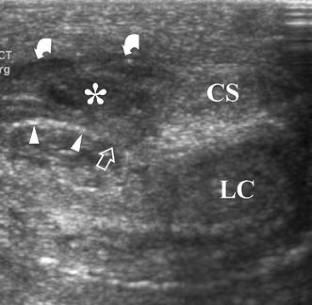

Injury to the penis may result from penetrating or nonpenetrating trauma. Nonpenetrating injury to the erect penis can produce albugineal tear, intracavernous hematoma or extraalbugineal hematoma from rupture of the dorsal vessels. Nonpenetrating injury to the flaccid penis usually follows blunt perineal traumas producing extratunical or cavernosal haematomas, or cavernosal artery tear followed by high flow priapism. Differential diagnosis between albugineal tear and other penile injuries must be obtained as soon as possible, since early surgical repair of albugineal tear reduces significantly the rate of postraumatic curvature and fibrosis. Ultrasonography (US) is able to detect the exact site of the tear in most patients as an interruption of the thin echogenic line of the tunica albuginea. Other imaging techniques are rarely required in the clinical practice. Color Doppler US is the imaging modality of choice to evaluate patients with high flow priapism. Focal or diffuse cavernosal fibrosis can be identified with US as echogenic areas in the cavernosal bodies. Postraumatic erectile dysfunction can result from fibrotic changes, nerve and vascular impairment or both. Doppler evaluation of penile vasculature is required in young patients with postraumatic impotence before surgical revascularization procedures.

Fig. 3

Fig. 4